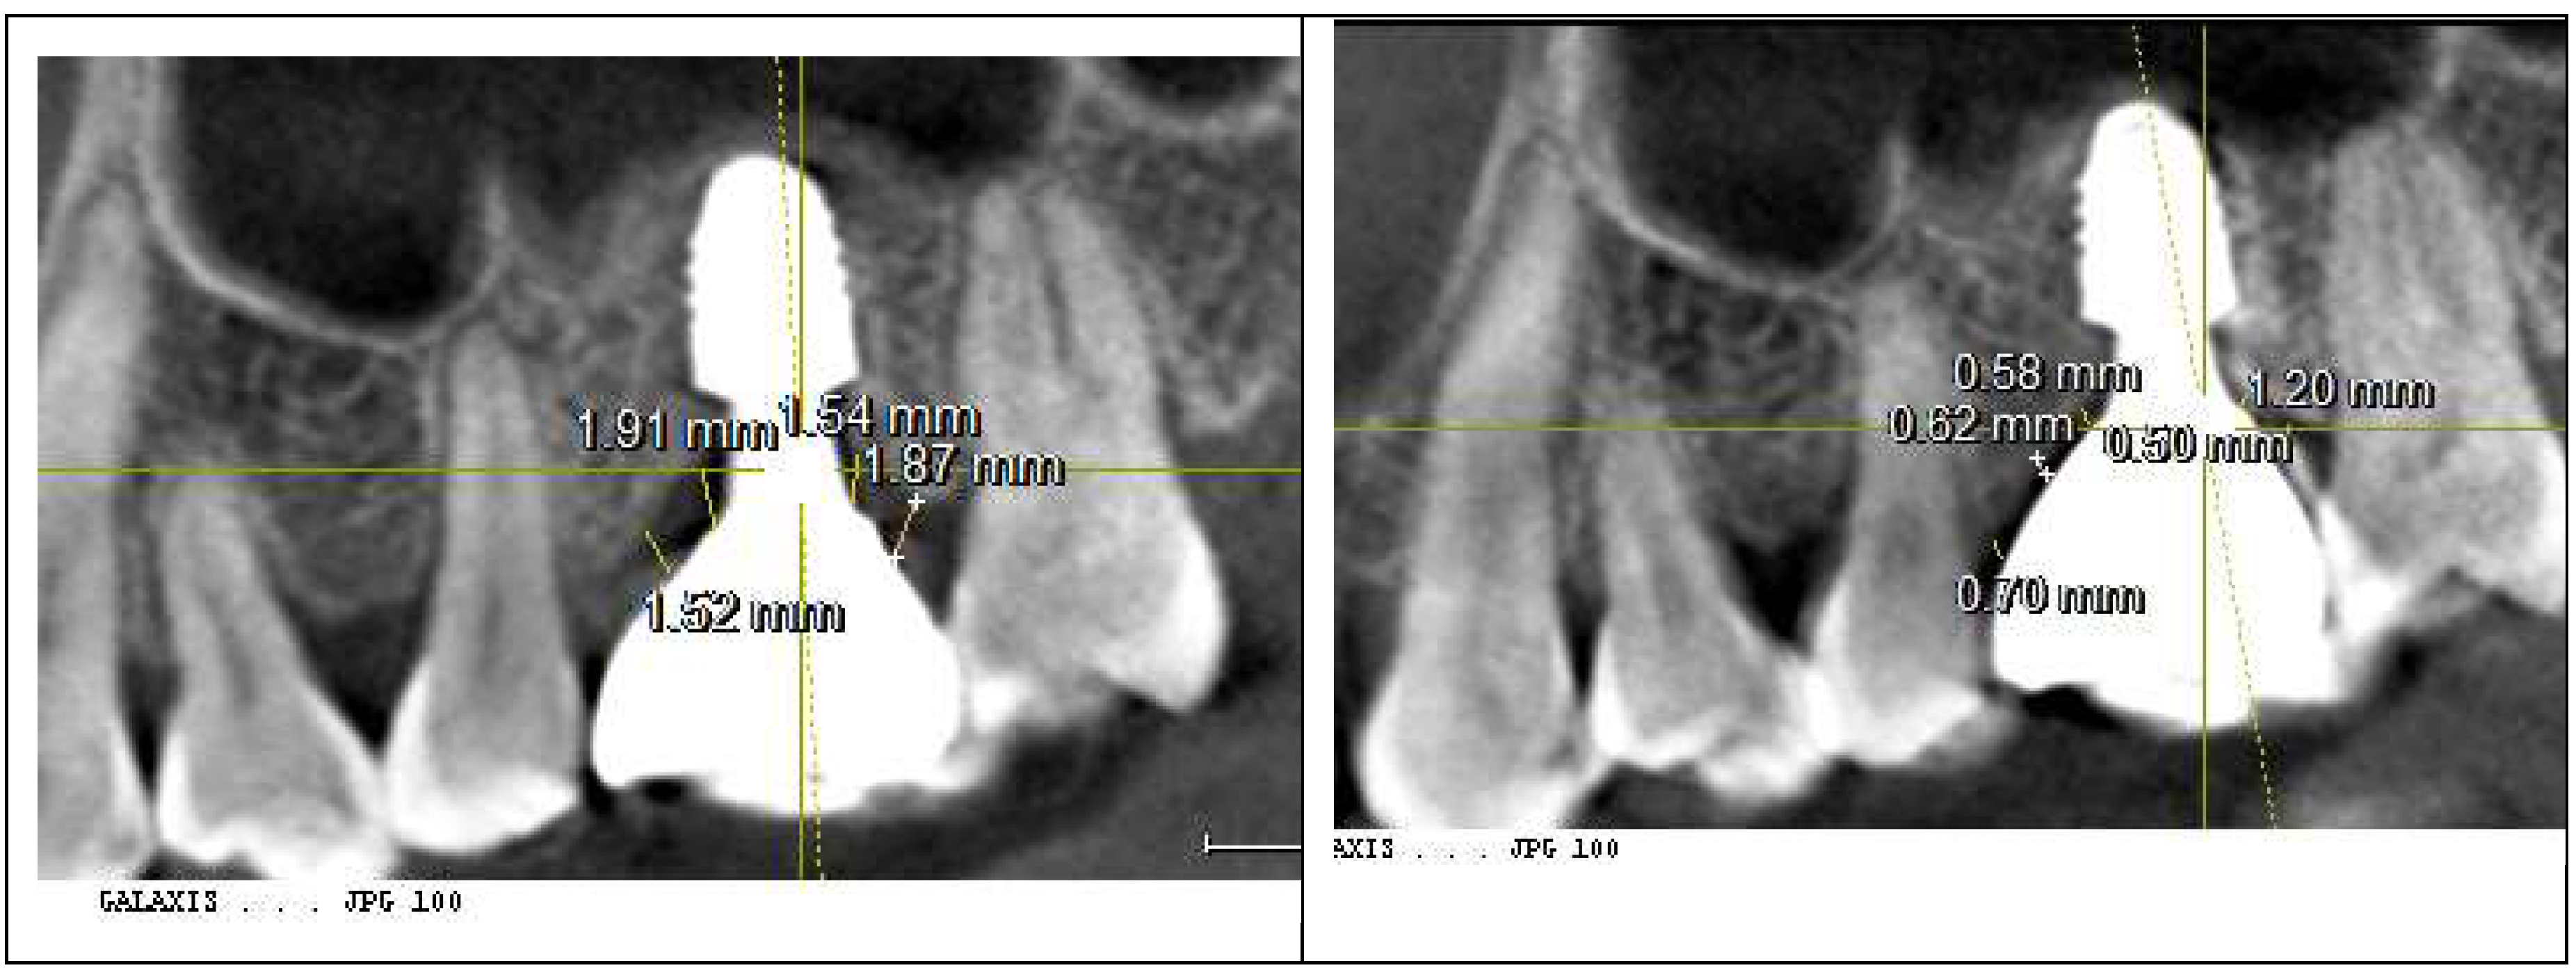

To assess peri-implant soft tissue structure and bone topography, a Cone-Beam Computed Tomography (CBCT) scan was performed, focusing on the Crest to Restoration Distance (CRD)—the vertical distance between the implant restoration and the crestal bone—to identify the optimal treatment approach. The results are summarized in

Table 1.

presents the measurements of the Crest to Restoration Distance (CRD), which quantifies the vertical distance between the implant restoration and the crestal bone. The values are divided into central CRD (cCRD) and peripheral CRD (pCRD) to distinguish the dimensional variations along the implant interface. These measurements are taken at both central and peripheral locations, evaluating the mesial (M), distal (D), buccal (B), and lingual (L) aspects around the implants of the upper left first molar and lower first molar. The data were collected from the CBCT scan conducted on October 26, 2021.

Measurement of Crest to Restoration Distance (CRD)

CRD refers to the vertical space between the crestal bone and the implant restoration. It is measured at two locations: centrally (cCRD) and peripherally (pCRD) to evaluate dimensional variations along the implant interface.

The CRD for the upper left first molar implant was consistently larger than that for the lower right first molar implant. The central CRD (cCRD) difference was 0.97 mm (1.48 mm – 0.51 mm), while the peripheral CRD (pCRD) difference was 0.90 mm (1.97 mm – 1.07 mm). As no CBCT-based CRD measurements exist in the literature, a clinical study by Won, analyzing CRD (or Soft Tissue Thickness, STT) in 20 cases of subcrestally placed implants with stable outcomes over two years, served as a reference. That study reported an average pCRD of 0.6 mm and cCRD of 0.3 mm (

The analysis indicated that the increased CRD in the upper left first molar implant likely contributed to peri-implant mucositis. To address this, the restoration was remade to adjust the CRD to the optimal range. A new restoration with a 4.5 mm diameter, 3 mm gingival cuff abutment was fabricated and delivered to the patient (

Figure 5).